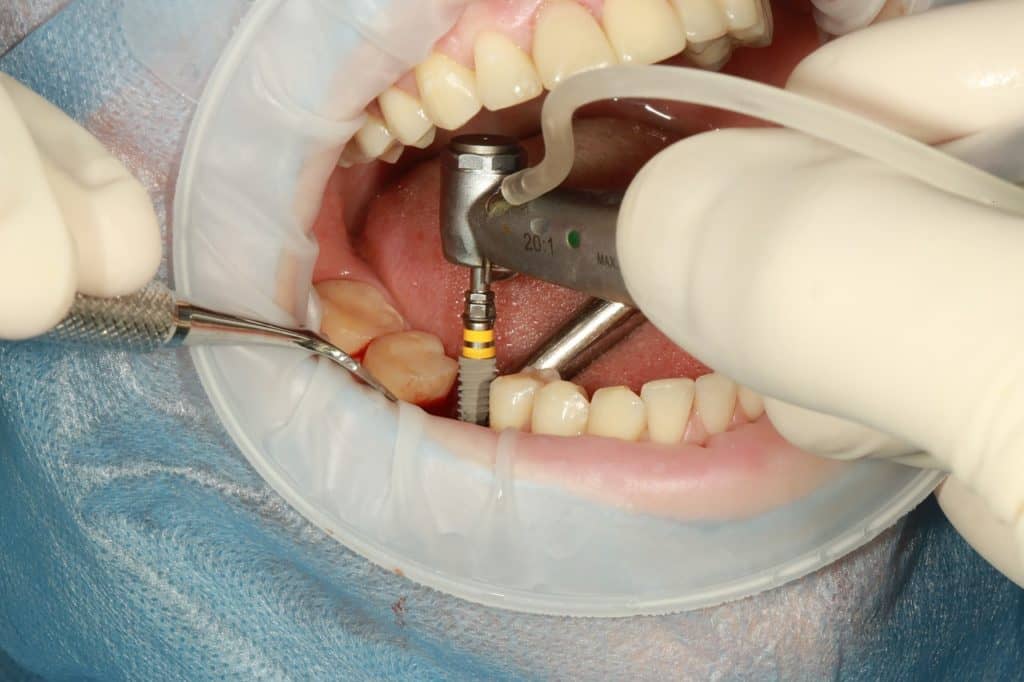

The second way to cover a missing tooth is to get a dental implant and as the name suggests mimics a tooth, so everything from eating, brushing your teeth and talking feels natural. It looks natural and feels natural. Over the course of a few months the area will then heal before abutment is applied, to which a crown will be cemented.

The focus for an implant is the missing tooth, so no work is needed on surrounding teeth in the same way a bridge would be used.